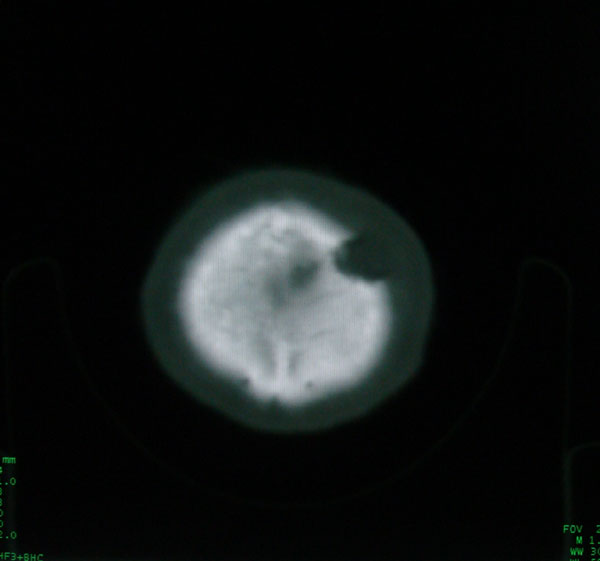

以下是引用zhangzhongshou在2008-6-7 12:49:00的发言:[br]左顶骨嗜酸性肉芽肿可能性大,建议ect及其他检查,除外转移瘤的可能。

以下是引用拾荒者在2008-6-7 13:05:00的发言:[br]左侧顶骨局限性骨质缺损,边缘锐利,无硬化边,周围软组织轻度肿胀,无明显软组织肿块及骨膜反应,考虑嗜酸性肉芽肿可能。